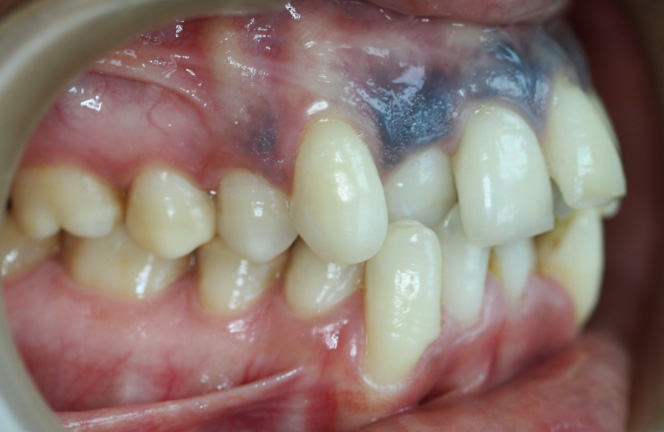

After-treatment images

After completion of orthodontic treatment, the patient showed:

• Properly aligned teeth

• Improved mouth closure

• A natural smile arc with improved esthetics, appearing even better than veneers